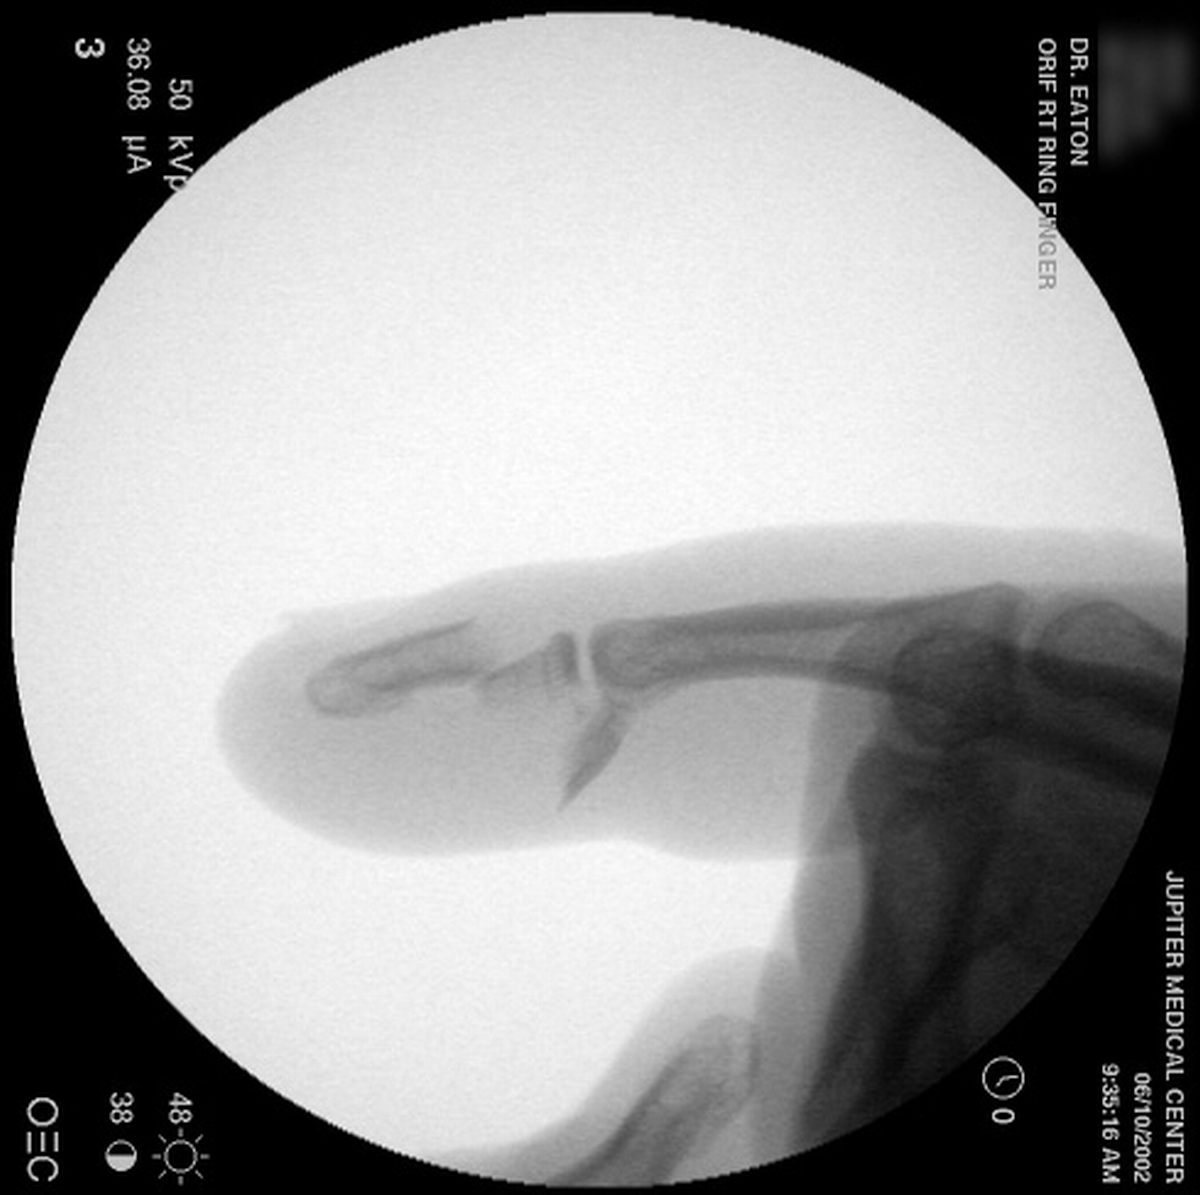

| A wire was passed through the dorsal proximal pin track and then around the palmar pins. After reduction and tightening this wire, the pins were advanced to engage the dorsal cortex. |

| Wiring was used to offset the strong pull of the flexor insertion. |

| All pins were cut below the surface of the skin. |